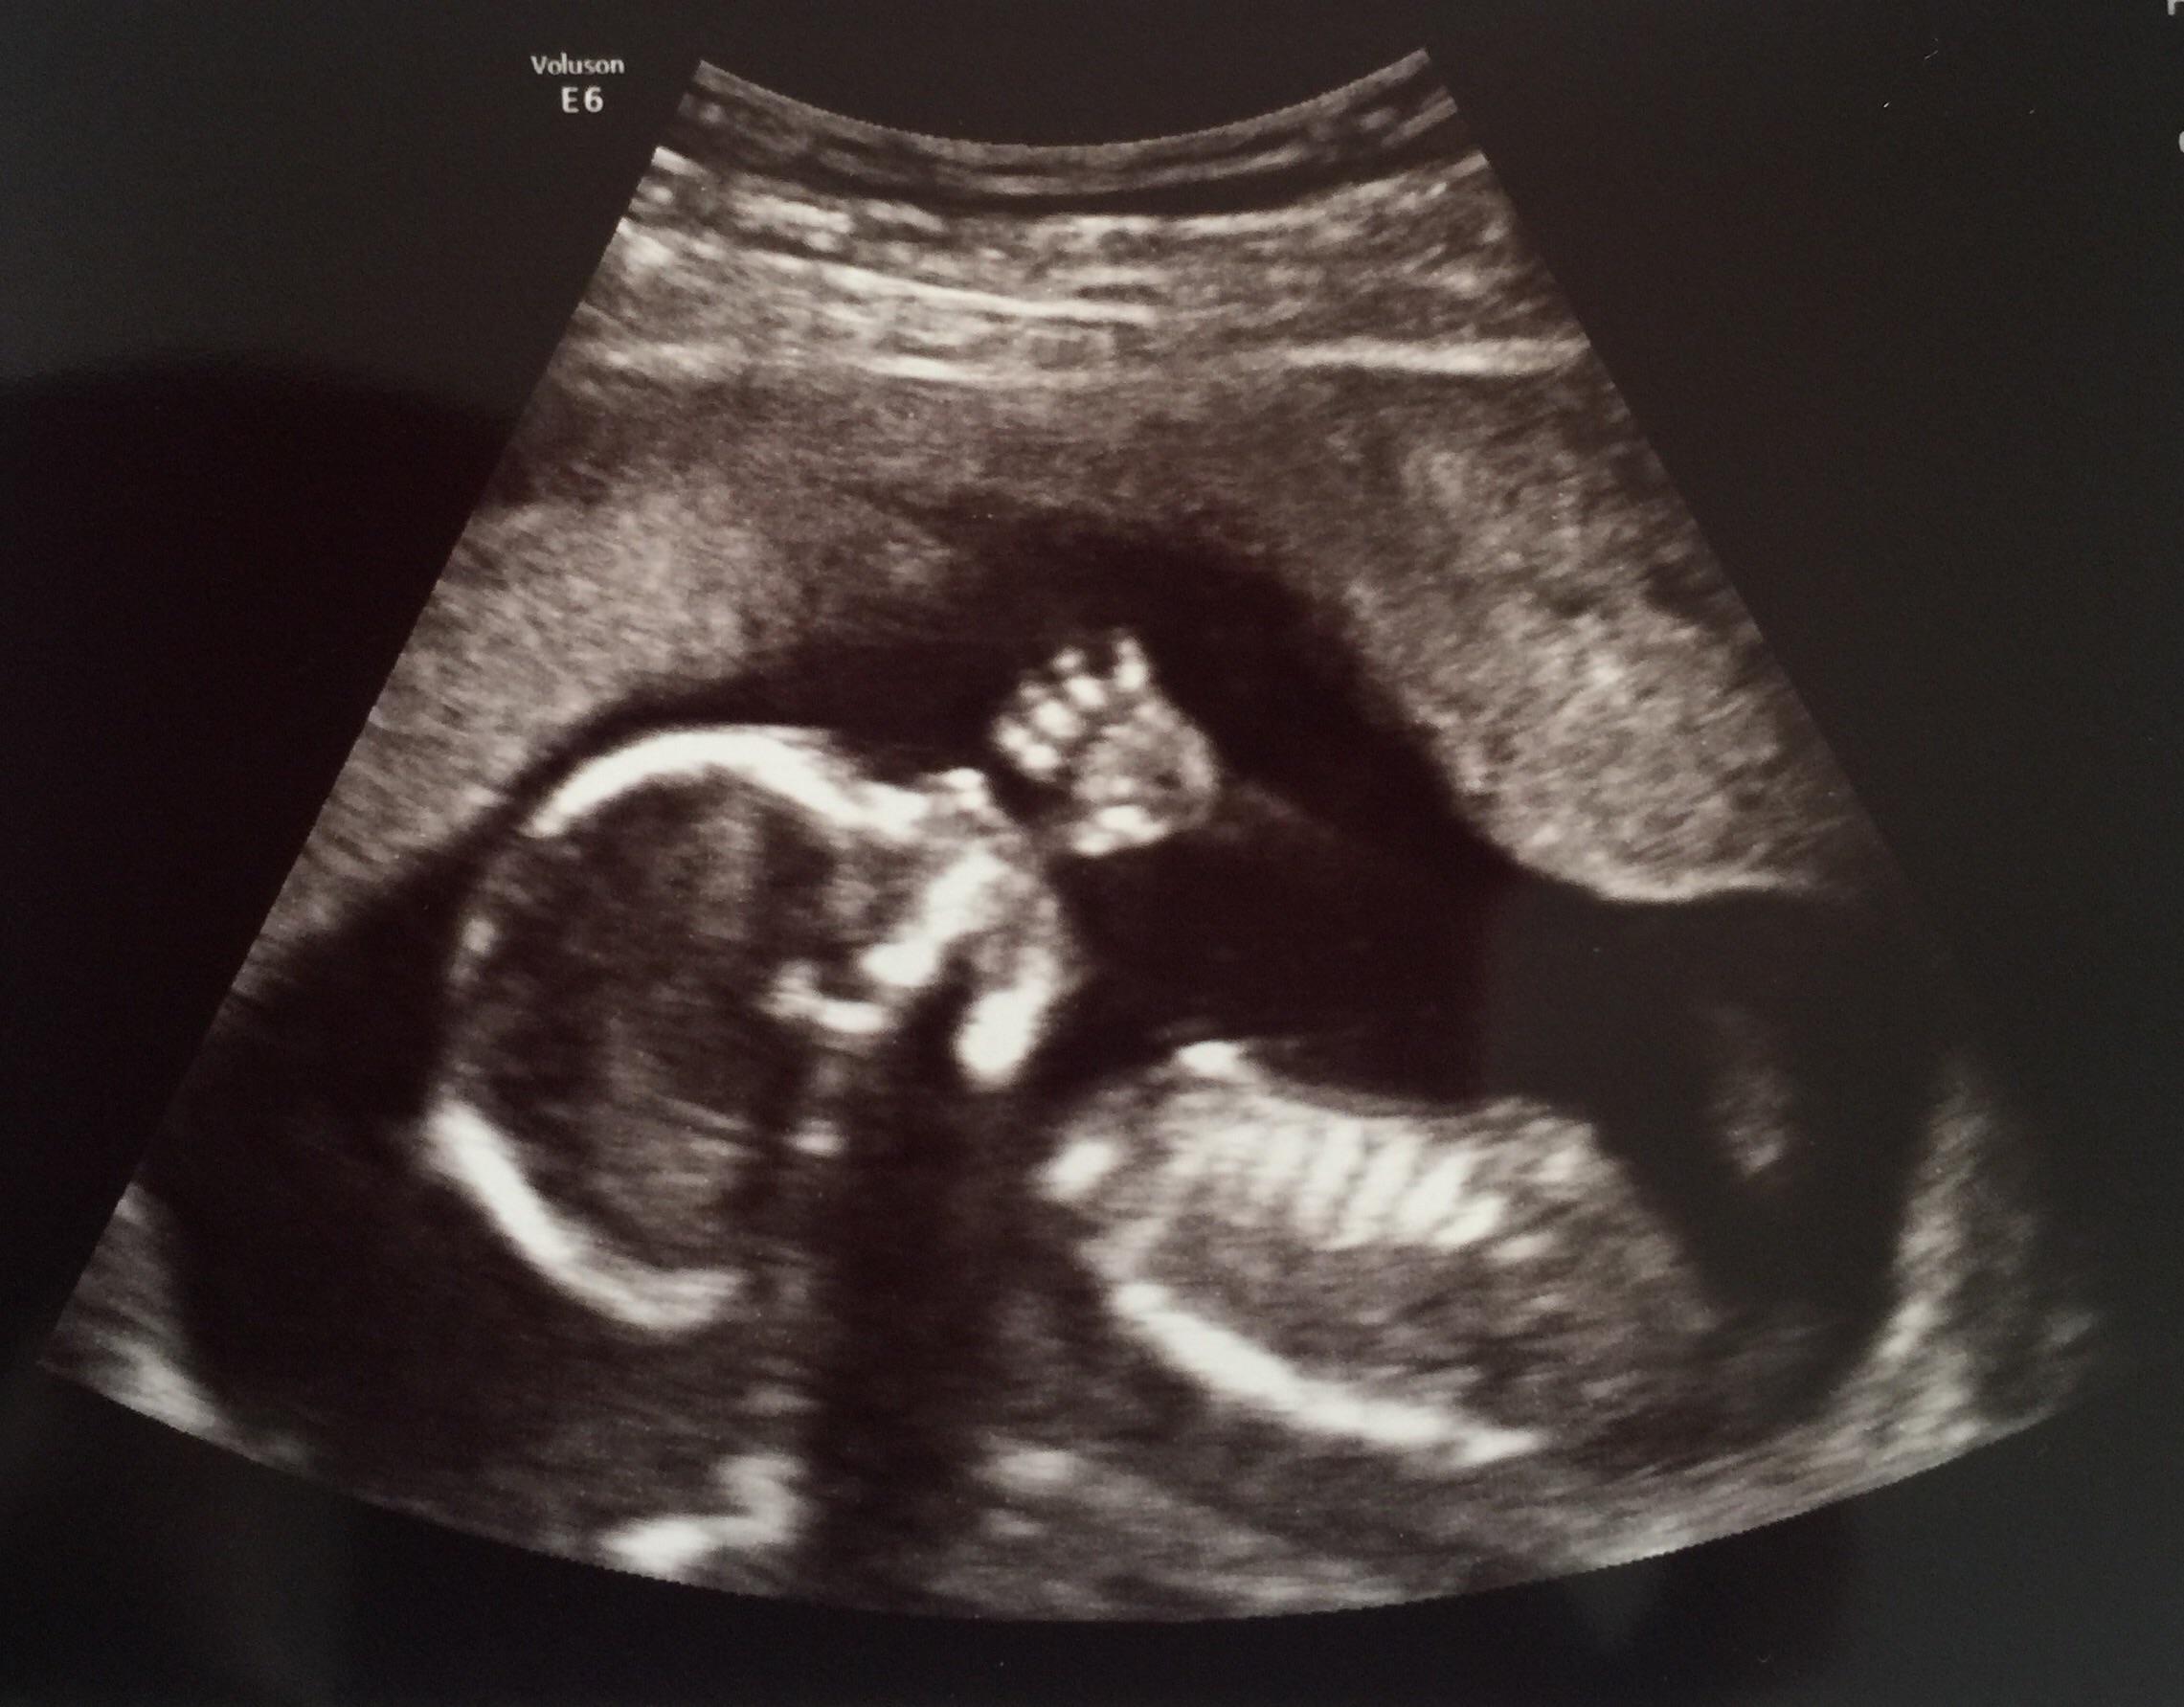

We had our scan on Tuesday and this babe would not stop moving! We're measuring a week ahead so we might be looking at a November. We will find out the sex at our reveal party this Sunday! I'm so anxious to start shopping for little one.